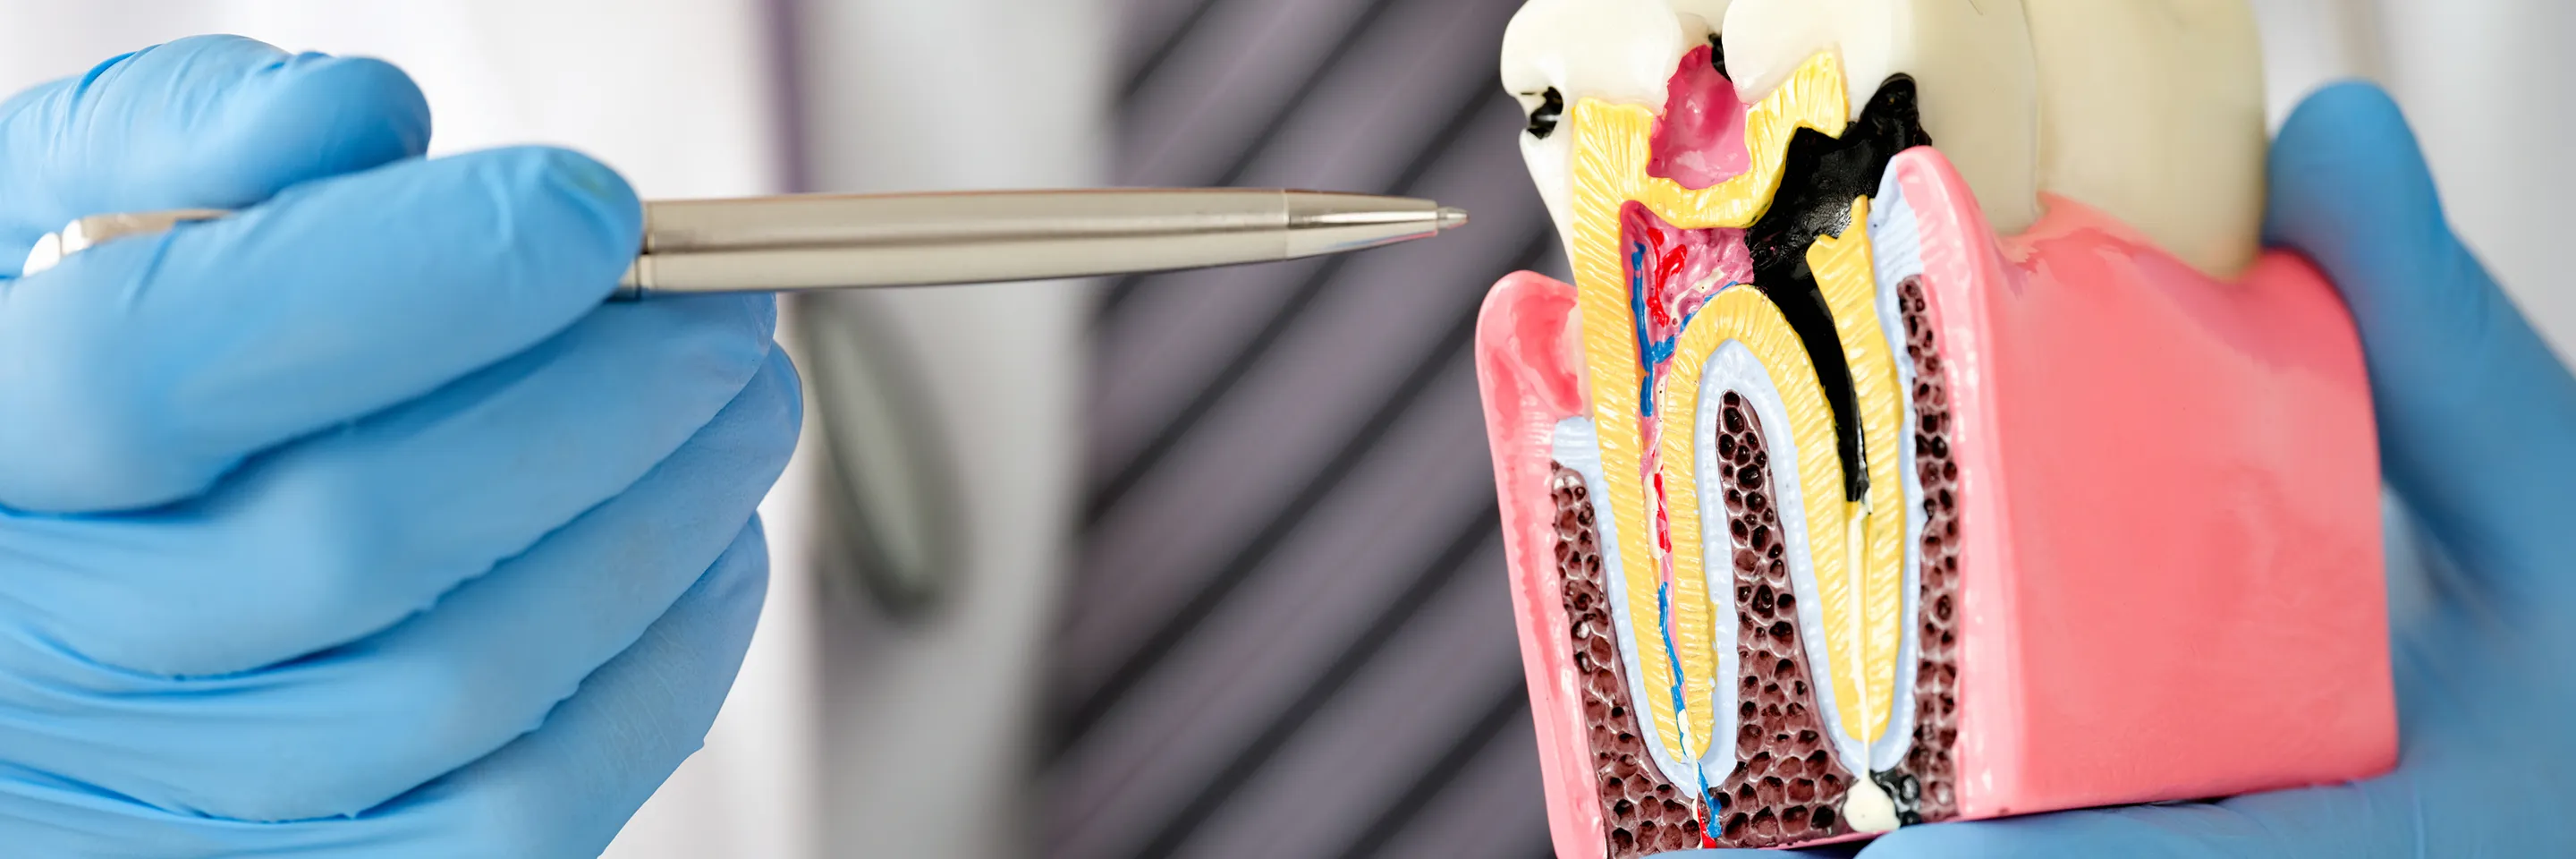

虫歯は放置すると進行し、最終的には歯を失う原因となります。しかし初期段階で発見し、適切な治療を行えば、歯を長く保つことが可能です。当院では視覚的にわかりやすい説明を重視し、患者様ご自身が納得した上で治療を受けられる環境を整えています。

当院では、初診時に口腔内写真撮影、パノラマレントゲン、CT撮影を行い、お口の状態を詳細に把握します。CT撮影により、目に見えない部分の虫歯や、歯の根の状態まで正確に確認できます。特に、神経に近い虫歯や根の治療が必要なケースでは、CTによる精密な診断が治療成功のカギとなります。

高倍率ルーペによる精密治療

撮影した画像をもとに、現在のお口の状態と治療方法をわかりやすくご説明します。治療期間や費用、治療のメリット・デメリットについてもお伝えし、患者様と一緒に最適な治療計画を立てていきます。